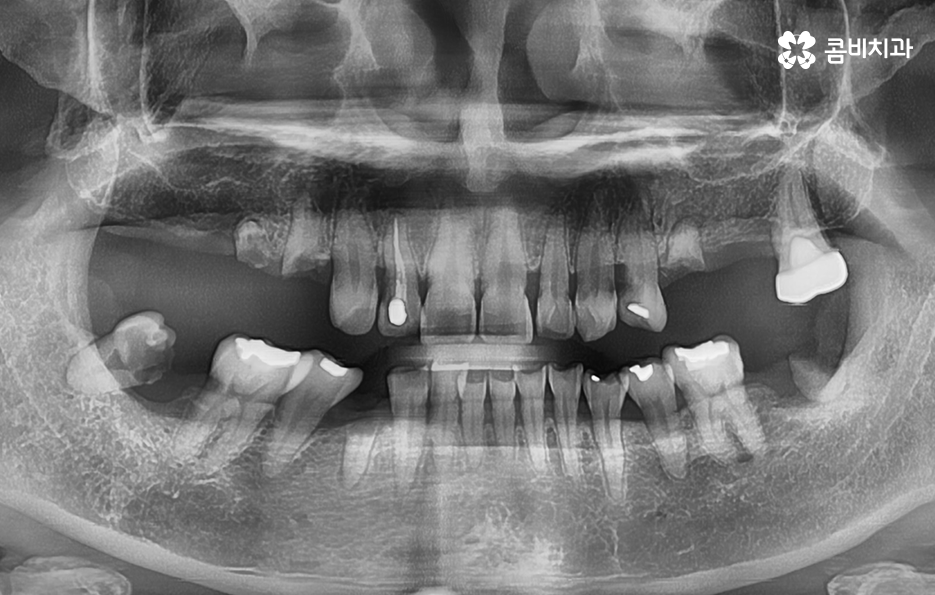

우리가 보편적으로 생각하게 되는 임플란트 치료기간의 경우 치아 하나를 상실하고 임플란트를 1:1로 치료할 때 예상 기간에 대해서 고려하게 되는 경우가 기본적인 접근 방법이라면 실질적으로 치과에서 임플란트를 하게 되는 연령대를 보더라도 보통 50대에서 60대 이후에 치아를 상실하게 되는 환자분들이 급증하기 때문에 위 사진의 사례처럼 여러 치아를 상실하고 임플란트를 식립하게 되는 경우도 많을 거예요